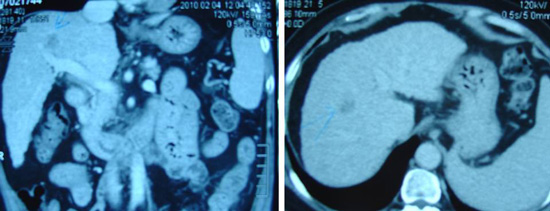

- CT scan on 5 March 2003, showed a 3.3 cm well-defined simple cyst in Segment 1 of her liver. In the upper pole of her right kidney was a 2.4 cm enhancing nodule with exophytic component.

- MRI of her abdomen done on the same day confirmed the presence of a 2.5×1.6×2.5 cm, irregularly enhancing mass in the upper pole of her right kidney with features suggestive of an underlying renal cell carcinoma.